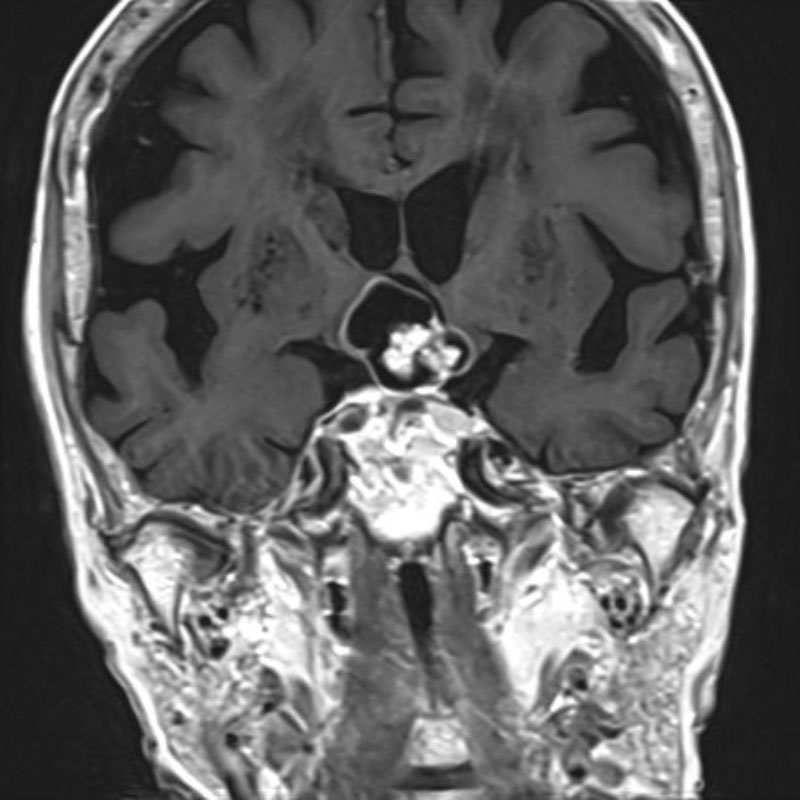

手術前1

手術前2